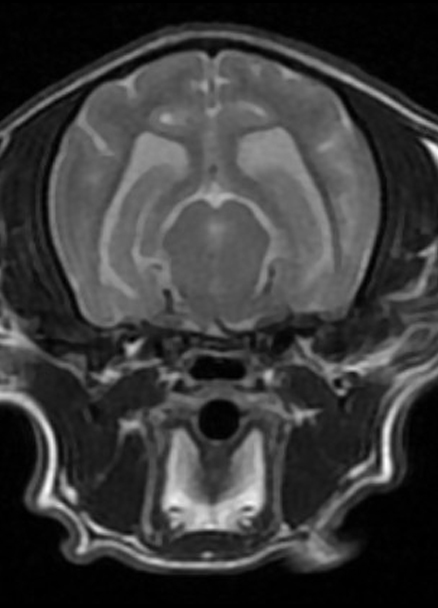

본 병원은 GE사의 1.5T 고해상도 자기공명영상장치(MRI)를 이용하여, 자기장을 이용한 비침습적 방식으로 뇌, 척수, 근골격계 등 다양한 연부조직을 정밀하게 영상화할 수 있습니다. MRI는 방사선을 사용하지 않아 반복 촬영에도 안전하며, 신경계 및 연부조직에 대한 탁월한 해상도를 제공하여 정확한 진단에 매우 유용합니다.

또한 본원의 MRI 장비는 GE사의 PROPELLER 기법을 도입하여 호흡이나 움직임에 따른 영상 왜곡을 최소화하면서도 검사 시간을 단축시켜, AI 기반 영상 처리 기술을 통해 노이즈를 줄이고 더욱 선명하고 명확한 영상을 획득할 수 있습니다. 이러한 기술적 강점을 바탕으로 마취 시간과 그에 따른 환자의 부담을 줄이면서도, 진단에 충분한 고화질 영상을 안정적으로 확보할 수 있습니다.